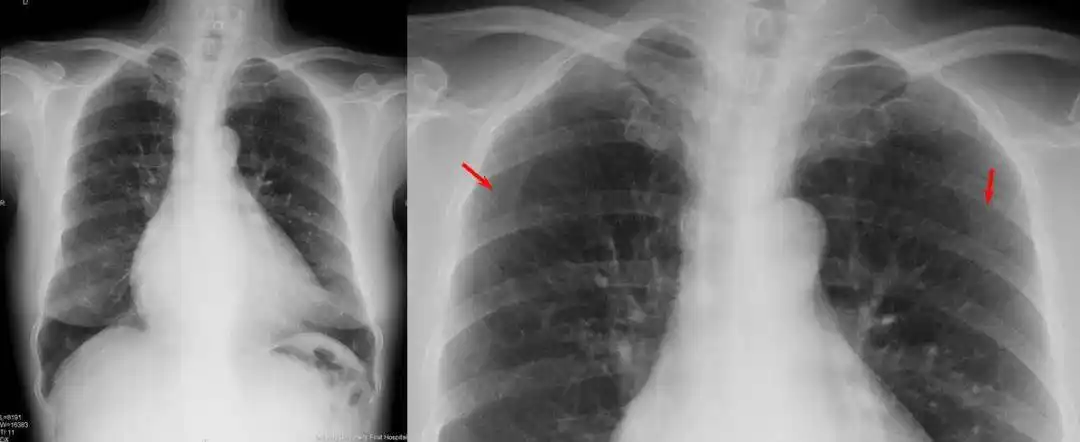

风心cr